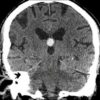

Nang keo não thất

Nang keo não thất - Ảnh 2

» Thông tin: Nữ giới – 70 tuổi.

» Lâm sàng: Đau đầu.